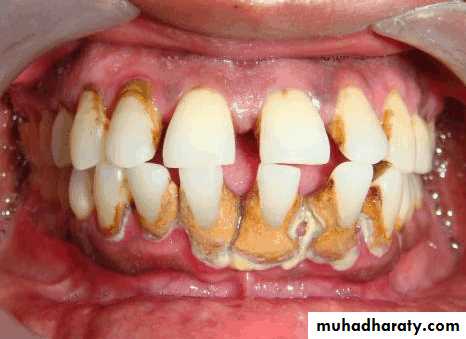

Evaluation of periodontium

Periodontal disease is one of the main etiologic factors in the loss of the teethA removable partial denture placed in the presence of active periodontal disease will contribute significantly to the rapid progression of the disease and the loss of the remaining teeth.

The causative factors must be eliminated, the disease process must be controlled before the fabrication of the prosthesis.

Examination findings that indicate possible need for periodontal treatment include

Pocket depth in excess of 3 mmFurcation involvement

Deviations from normal color and contour in gingiva, indicating gingivitisMarginal exudate

Potential abutment teeth with less than 2 mm of attached gingiva

Pulling of muscle or frena on attached gingiva